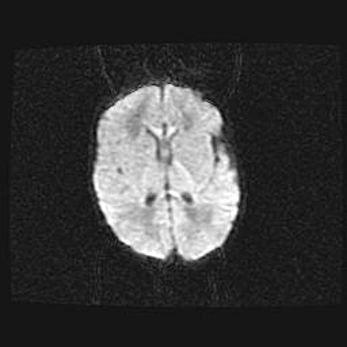

Сообщающаяся гидроцефалия. Кистозная энцефаломаляция головного мозга.

Возраст: 3 месяца 4 дня

Вес: 3100 г

Пол: женский

Окружность головы: 34 см

Срок гестации: 31 неделя

Кистозная энцефаломаляция головного мозга - одна из форм поражения головного мозга в детском возрасте. Характеризуется возникновением множественных и распространённых кист в коре, белом веществе и подкорковых образованиях головного мозга у плодов, новорождённых и детей раннего возраста. Развитие кистозной энцефаломаляции связано с внутриутробной асфиксией и гипотонией, родовой травмой, тромбозом синусов, пороками развития сосудов, инфекциями, сепсисом и другими причинами. Наиболее значимые инфекционные агенты: вирусы простого герпеса, цитомегалии, краснухи, токсоплазмы, энтеробактерии, золотистый стафилококк и другие.